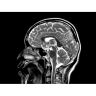

• РЧ-катушки, оптимизированные для исследования конкретных участков тела — элементы катушек высокой плотности располагаются вокруг исследуемых участков тела и при необходимости обеспечивают расширенный охват и оптимальное качество изображений при каждой процедуре.

• Радиологам достаются изображения великолепного качества, необходимые им для постановки точных диагнозов.